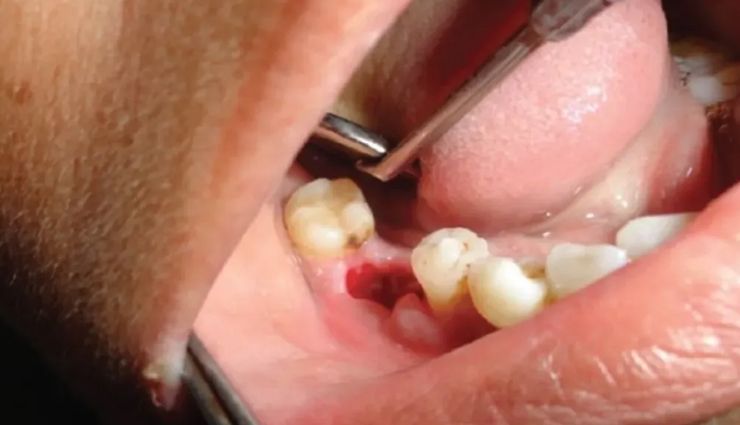

Such third molars can cause dental issues if they don't have enough space to come through or if they come through at an angle. This can cause pain, infection, and damage to other teeth, so removal is often recommended.

Your oral surgeon will make an incision in the gum tissue to access the tooth and may need to remove some bone to access the tooth root. The tooth may be divided into sections for easier removal, and any remaining debris will be cleaned out. The gum will then be stitched up, and you'll be given aftercare instructions.